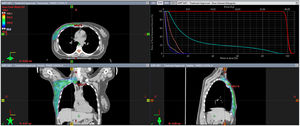

Radioterapia estereotáxica extracraneal (SBRT) ósea. Se trata del tratamiento con SBRT de la misma paciente, sobre la metástasis ósea única en escápula izquierda, la cual presentó al diagnóstico con una respuesta parcial al tratamiento sistémico. Se administraron 30 Gy en 3 sesiones. Corte de la planificación en axial, coronal y sagital. Adicionalmente el histograma dosis/volumen de la dosimetría.